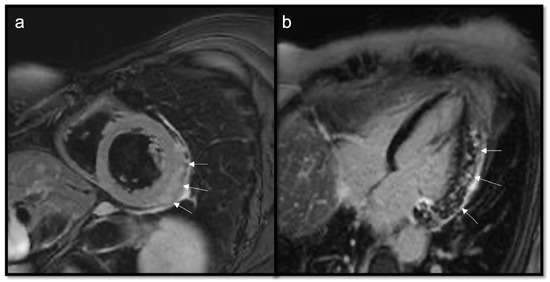

- To recognize fluid content such as a pericardial cyst or myocardial cyst (Figure 3)